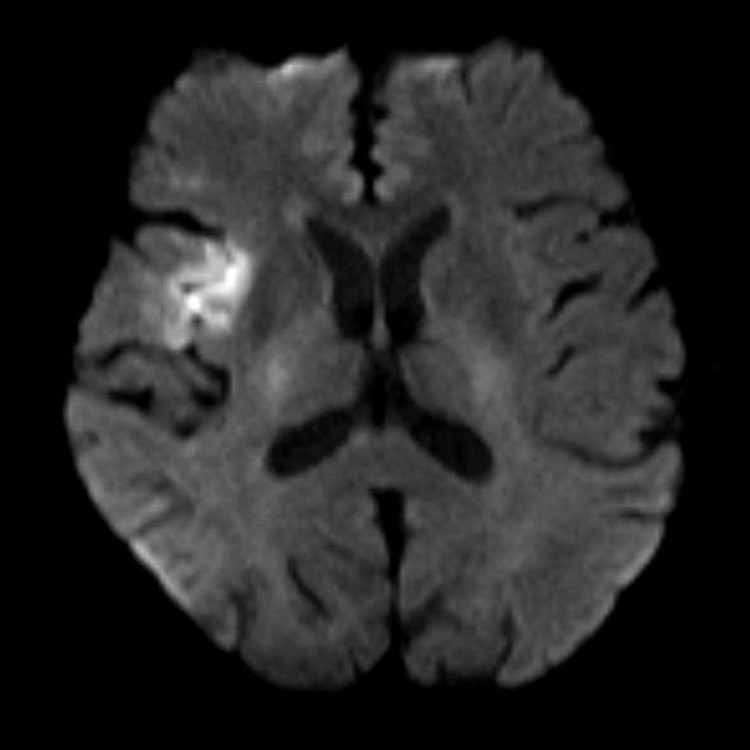

dot-quy-do-cao-1.jpg

dot-quy-do-cao-2.jpg

Hình MRI bệnh nhân T.L bị đột quỵ - Ảnh BVCC